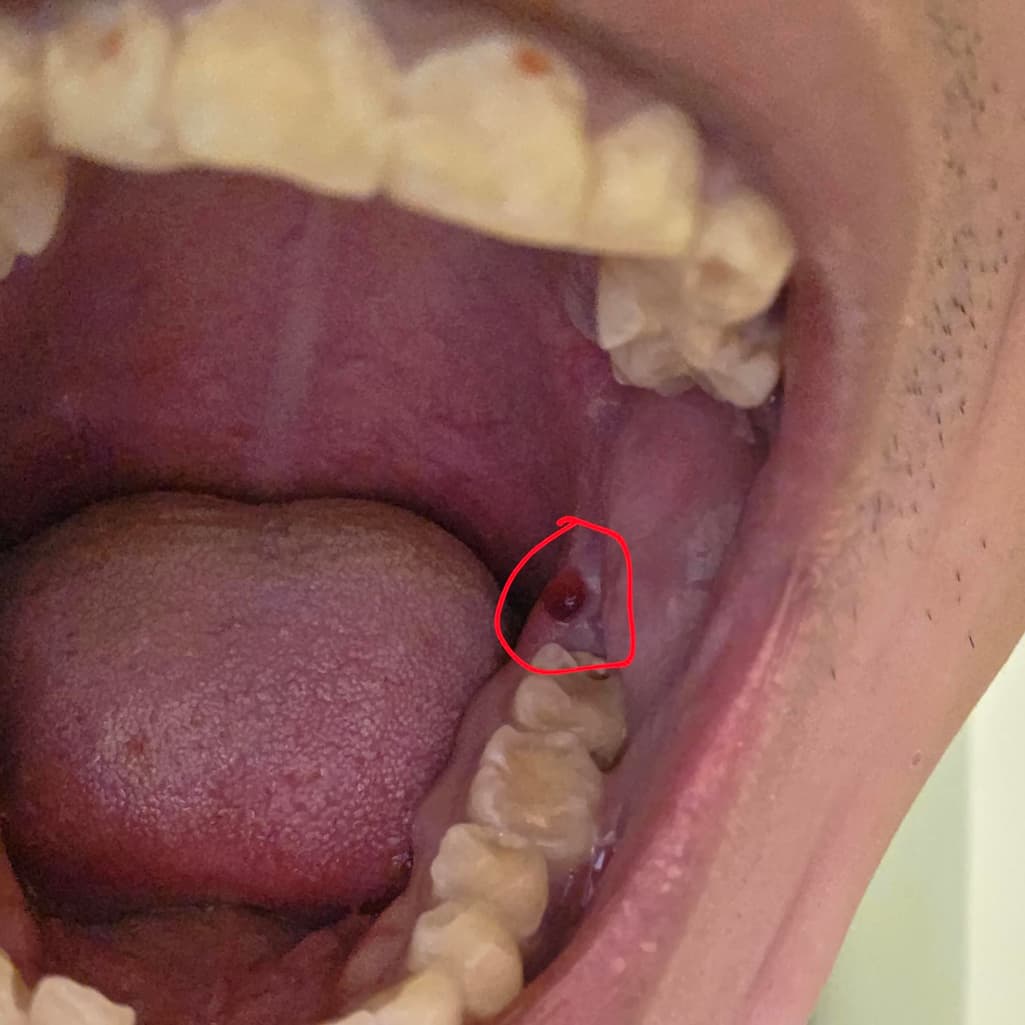

입 안쪽 붉게 상처난 부분 구강암일까요?

입 안 붉게 되있는 부분 구강암일까요?

구내염이나 다른 입병 중에 저런 증상이 있는건가요?

피가 나지는 않고 저렇게 붉게만 되어있고 혀로 만져보면 느낌이 있습니다.

위 사진만으로는 명확히 알 수는 없습니다. 크기가 커지거나 사라지지 않으면 치과 가보시면 됩니다.

구강암 아닙니다. 단순 물집 수포 입니다. 잇몸에 상처를 입어서 이런 물집이 생깁니다. 저절로 터지니 그냥두면 됩니다. 혹시 터질 때 피가 조금 스며 나올 수도 있습니다.

사진에 보이는건 잇몸이 치아에 씹혀서 피가 고인거 같습니다. 그냥 터트리면 문제가 없으니 너무 걱정하지마세요.

악성병소 여부는 조직검사를 해봐야 합니다 눈으로 봐선 어떤 이유때문인진 모르겠지만 혈종이 생긴것으로 보입니다